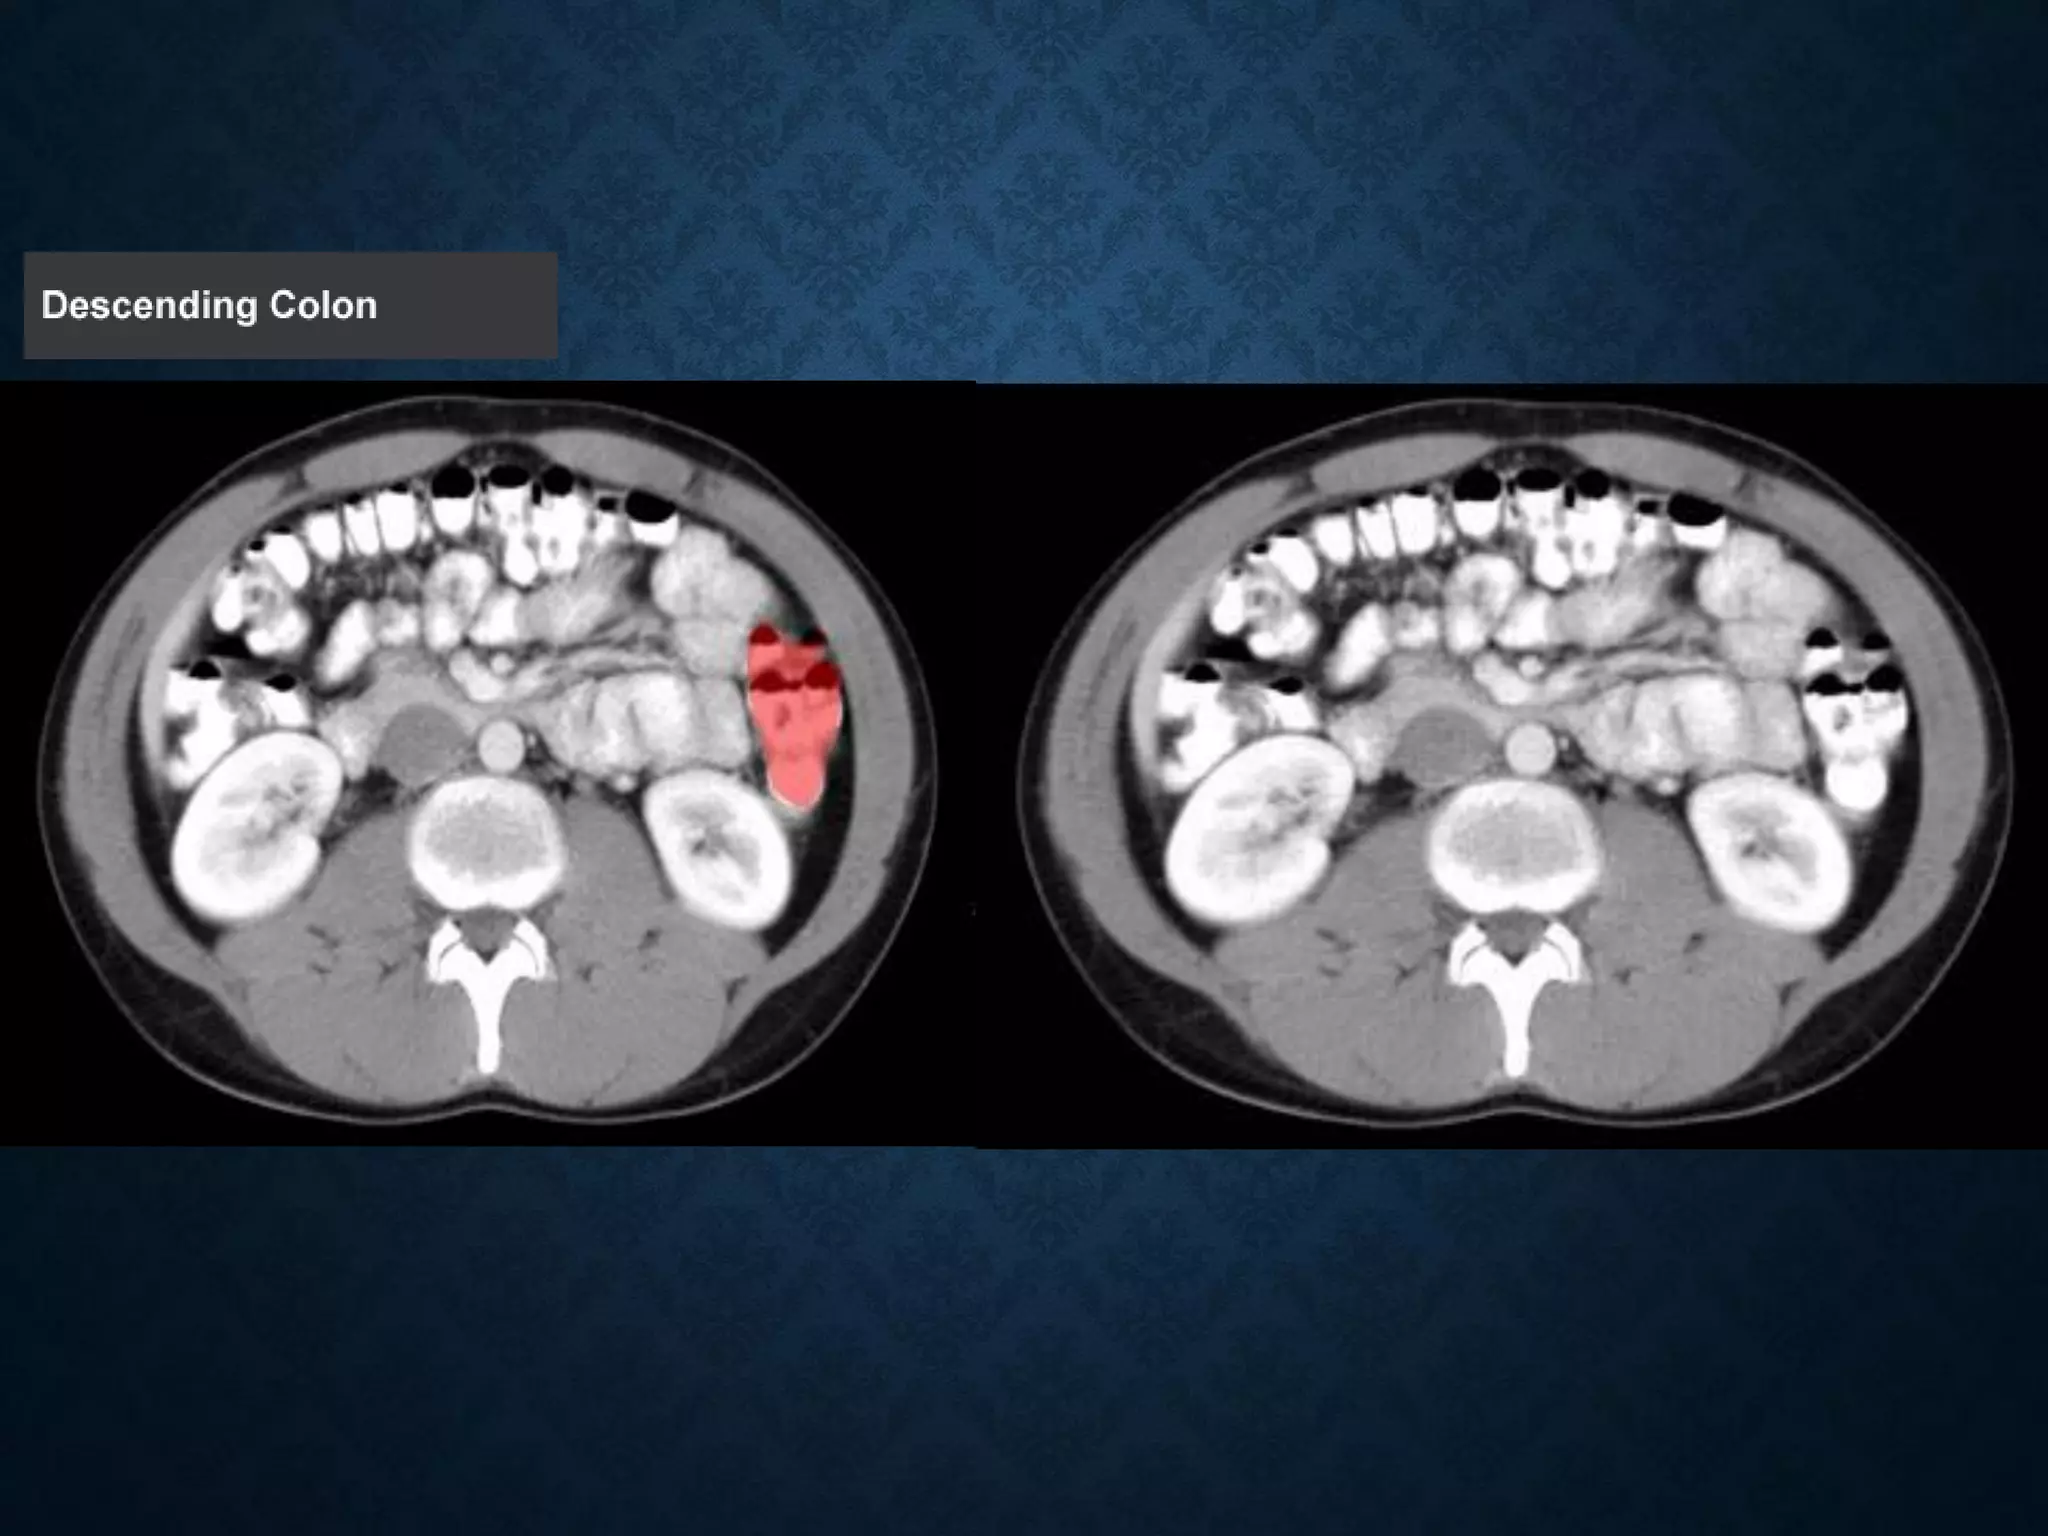

Identify the following structures in the body CT to the right. To view the location of the structure in the image click on

the label at the left and the structure will be indicated in the image. Abdominal CT scans typically begin just above

the diaphragm, so the first slice you see is of the lower chest.

Identify the followingstructures in the body CT to the right. To view the location of the structure in the image click on the label at the left and the structure will be indicated in the image. Abdominal CT scans typically begin just above the diaphragm, so the first slice you see is of the lower chest.